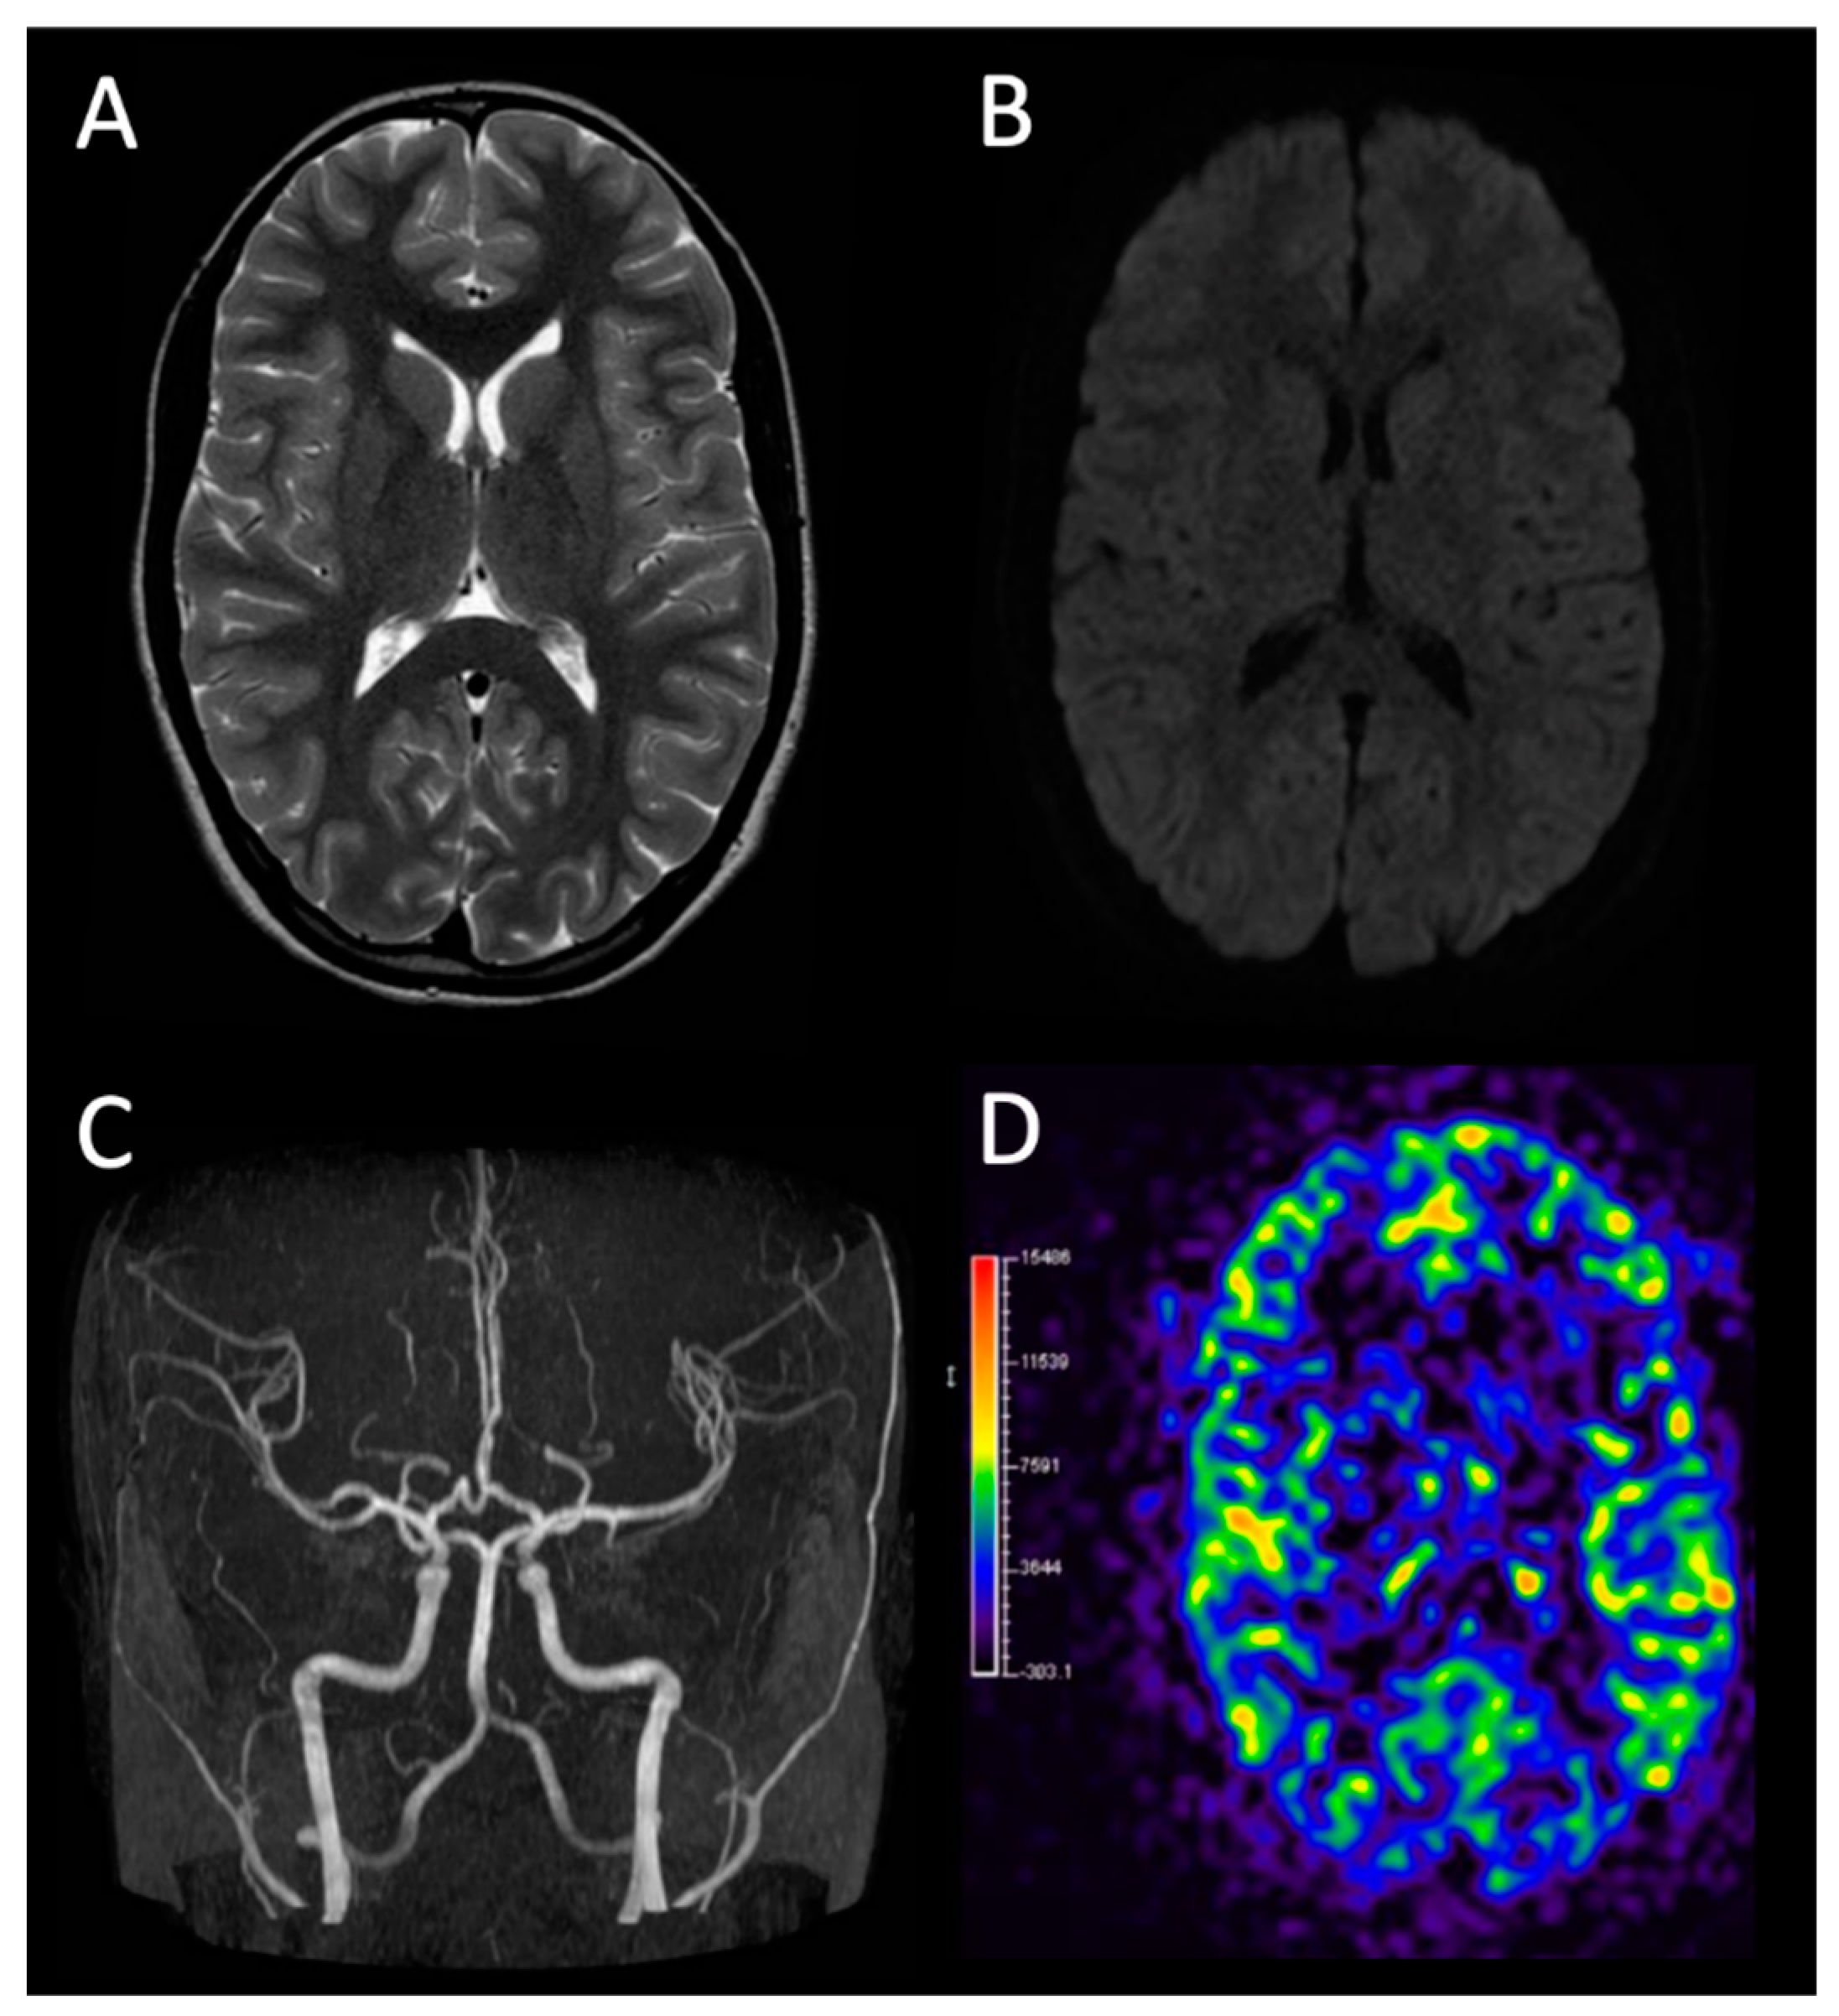

| Complete blood count and leukocyte count | Brain MRI |